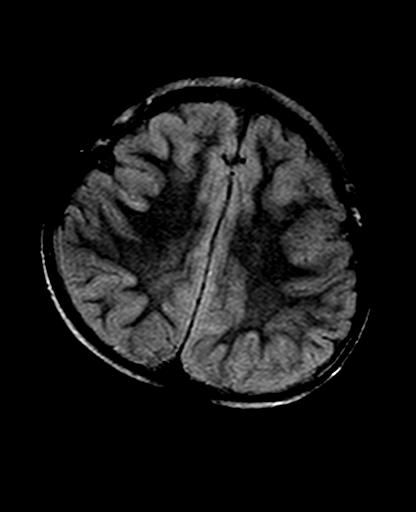

标题: PED2848:脑内病变2

头痛10天、间断呕吐2天。f 6岁

入科化验血清铜及铜兰蛋白均减低,脑脊液正常,血清神经原烯醇化酶明显增高。wbc:5.94x109/l、

mri未见明显异常。但临床支持考虑肝豆状核变性。